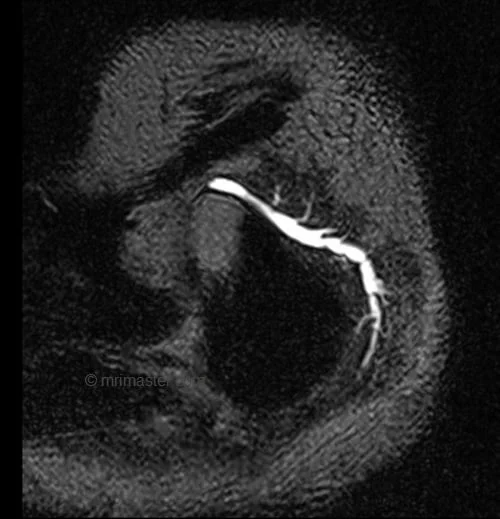

- Very useful for sialography imaging (.6MM 3D T2 SPACE with high TE)

T2 SPACE sagittal sequence used in sialography imaging